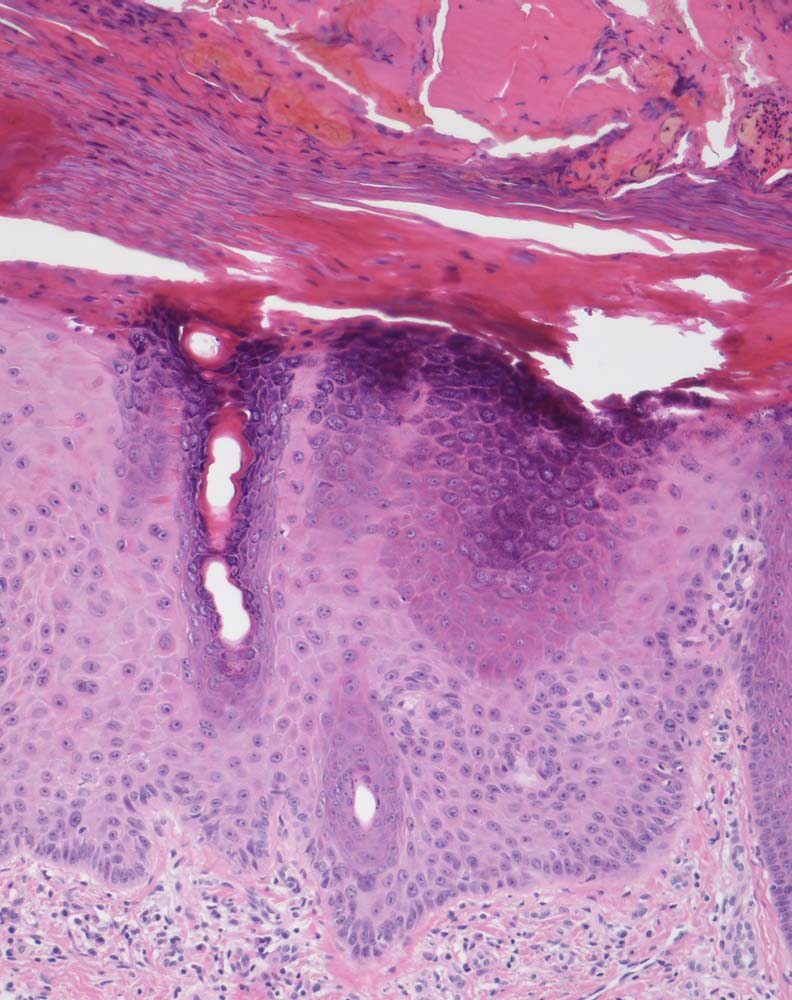

Die Epidermis zeigt obligat dysplastische Veränderungen. Die Dysplasie kann sich auf das untereste Epitheldrittel beschränken (leichte Dysplasie) oder die gesamte Epithelbreite betreffen (=bowenoide aktinische Keratose bzw. Carcinoma in situ). In der Dermis findet sich als Zeichen der chronischen UV Schädigung der Haut immer eine ausgeprägte solare Elastose. Das histologische Bild ist abgesehen von diesen zwei obligaten Befunden sehr variabel. Dyskeratotische Zellen und Mitosen finden sich häufig. Charakteristisch ist auch das Vorliegen einer alternierenden Para- und Orthokeratose, die unterschiedlich stark ausgeprägt ist. Manchmal findet man eine Atrophie der Epidermis mit schmalem Stratum corneum oder umgekehrt eine massive Hyperkeratose wie beim Cornu cutaneum. Akrosyringium und innere Abschnitte der Haarfollikel sind von den dysplastischen Veränderungen ausgespart. Die Epidermis zeigt häufig eine unregelmäßige Hyperplasie mit in das Stratum papillare reichenden Knospen. Bei Ausdehnung der Dysplasie entlang von Haarfollikeln in die Tiefe, können sich bei zu oberflächlicher Abtragung der Läsion Lokalredzidive ausbilden.

Unterschieden werden mehrere histologische Subtypen der aktinischen Keratose: hypertropher, atropher, bowenoider, akantholytischer und pigmentierter Typ. Beim gleichen Patienten können unterschiedliche Subtypen vorkommen.

Der Übergang in ein frühinvasives malignes Plattenepithelkarzinom mit Metastasierungspotential ist histologisch nicht immer einfach erkennbar. Einzelzellinfiltrate, welche die Basalmembran durchbrochen haben, eine Stromadesmoplasie oder Zellnester innerhalb der retikulären Dermis werden als Merkmale für invasives Wachstum gewertet.